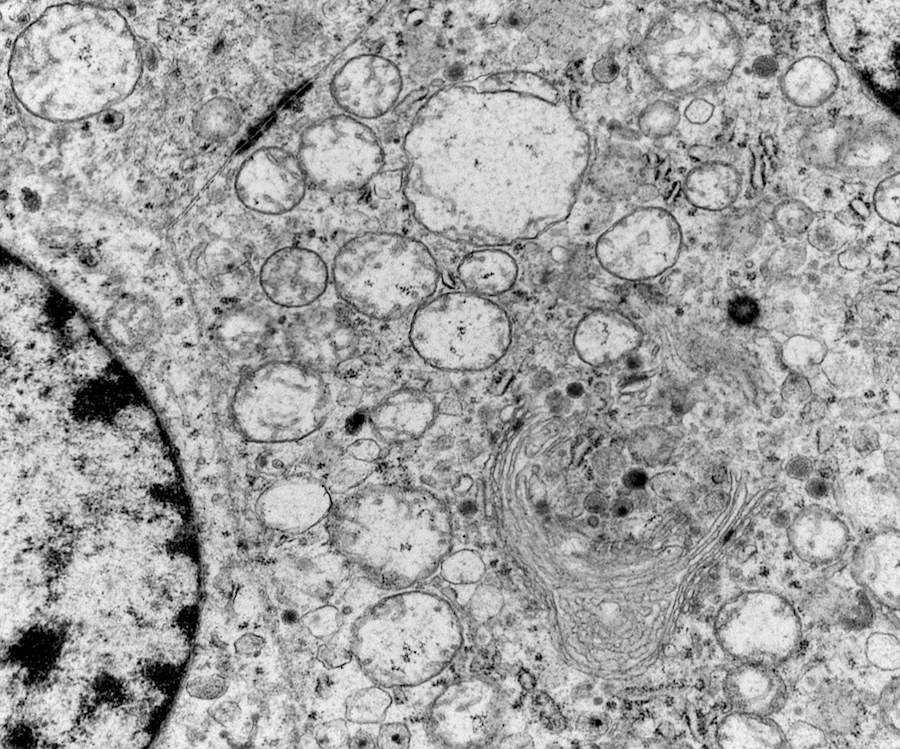

Electron microscopy description

- Chief cells are polygonal with well developed rough endoplasmic reticulum, prominent Golgi complex and abundant cytoplasmic neurosecretory granules (Arch Pathol Lab Med 1980;104:46)

- May have giant mitochondria with paracrystalline inclusions

- Sustentacular cells wrap around chief cells and lack neurosecretory granules

- No desmosomes

Electron microscopy images